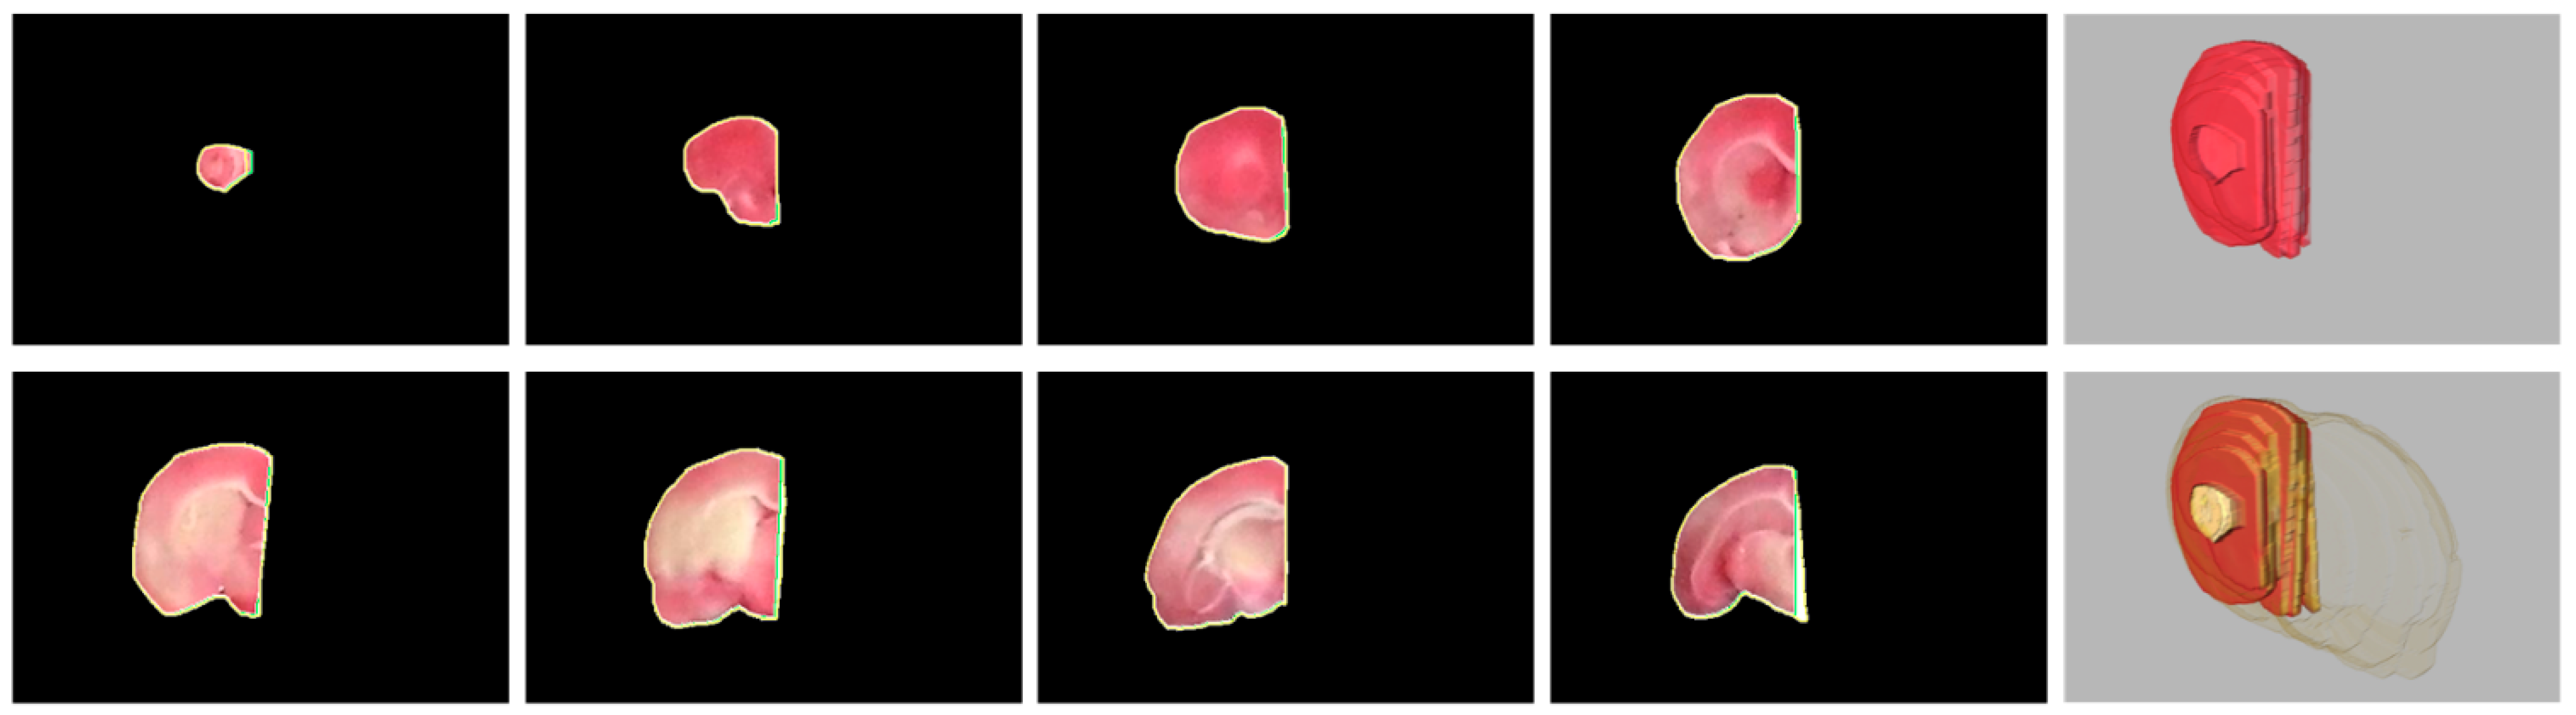

3. Hemisphere Segmentation

3.1. Challenges

- Due to the manual placement of the rat brain slices, the midline is randomly oriented, not vertically.

- The rat brain can be seriously distorted due to the infarction of the induced stroke so that the midline is convoluted.

- The midline exhibits a similar color tone to its surrounding tissues and is visible in short segments to the naked eyes.

- There are merely few anatomically salient structures around the midline that can provide meaningful information for the identification.

4.4. Evaluation of Rat Hemisphere Segmentation